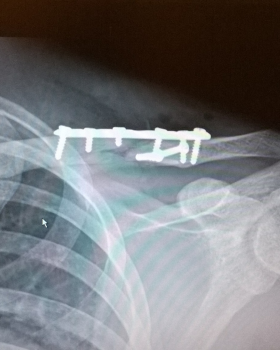

Each of these conditions may vary in severity and thus may require different types of medical or rehabilitative treatments. In extreme cases a clavicle fracture may also be present due to the traumatic nature of the injury. This particular condition must be ruled out with radiographic testing to ensure each injury is properly managed and that each player returns to play as safe and as fast as possible. In extreme cases surgery is required to maintain the individual’s overall structure of their clavicle and long-term function of the shoulder.

The radiographs below are of a 39 year old male that collided into the boards with an out stretched arm fracturing his clavicle into 4 pieces. After his surgical intervention and physical therapy program he returned to the ice with no physical restrictions or limitations.